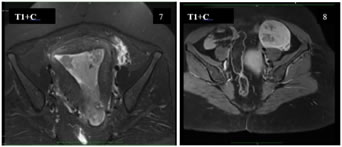

A 40 years old nulliparous premenopausal woman, presented to the gynaecology OPD with a chief complaint of abnormal uterine bleeding and pain in the lower abdomen, predominantly towards left side since an year. The patient had no significant relevant past history or risk factors. The clinical examination of the abdomen revealed no palpable mass. Abdominal ultrasound revealed a solid heterogeneously hypoechoic mass lesion arising from the left ovary, measuring approximately 55x53x50mm and showing moderate colour flow on colour doppler. A moderately enlarged uterus with increase in endometrial thickness was also identified (24 mm). No suspicious abdominal lymphadenopathy was noted. MRI Pelvis showed a single large well defined moderately enhancing, mixed predominantly solid lesion measuring approximately 60x58x53mm (MLXCCXAP) in the left adnexa, which is heterogeneously hypointense on T1W, Isointense with central hypointense areas on T2W, heterogeneously hyperintense with central hypointense areas on T2W/STIR and showing no restricted diffusion on DWI. Uterus appears moderately enlarged with multilobulated heterogenous diffuse moderately enhancing solid areas and non-enhancing cystic areas within the endometrial cavity. No suspicious pelvic lymphadenopathy was noted. Serum CA-125 concentration was elevated,95 U/mL (normal range <35 U/mL). After the positive frozen section pathological examination of the left ovary, the patient underwent a total abdominal hysterectomy, bilateral salpingo-oophorectomy, bilateral pelvic and para-aortic lymphadenectomy, and omentectomy. Pathological findings revealed a well-differentiated endometrioid carcinoma of the left ovary and a well-differentiated endometrioid carcinoma of the endometrium. The patient did not receive any adjuvant chemotherapy or radiotherapy and was suggested for a regular follow-up. Up to the last follow-up visit (April 2021), the patient had no recurrence.

Figure 5: T1W Thickened heterogenous endometrial cavity; Figure 6: T1W Heterogeneously hypointense, mixed predominantly solid lesion involving the left adnexa; Figure 7: T2W Mixed solid and cystic areas in the endometrial cavity; Figure 8: T2W Mixed predominantly solid lesion involving the left adnexa showing Isointense with central hypointense areas;